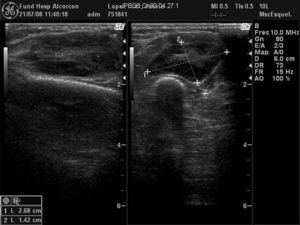

Mujer de 73 años con antedecente de melanoma coroideo en ojo derecho en 1999 tratado con braquiterapia. En mayo de 2008 acudió por nódulo en antebrazo izquierdo de 4 meses de evolución. A la exploración física se objetivaba un nódulo no doloroso a la palpación que parecía depender de la musculatura extensora. El hemograma, la bioquímica y el examen de orina fueron normales. La VSG de 26mm (0–20). La Rx del antebrazo (fig. 1) evidenció una masa densa en partes blandas sin erosión ósea. La ecografía (fig. 2) objetivó una tumoración ovalada, sólida con flujo arterial en su interior. La RM (fig. 3) mostró una masa sólida hiperintensa en T1, levemente hiperintensa en T2 y algo más brillante en STIR.

Ecografia antebrazo izq: Se observa una tumoración ovalada, sólida de 36×26×14mm, bien delimitada con flujo arterial en su interior. En el plano muscular lateral del antebrazo izquierdo se observa una tumoración ovalada sólida de 36×26×14mm, bien delimitada por un anillo ecogénico, predominantemente hipoecogénica respecto a la musculatura adyacente, con una zona central hiperecogénica. Se observa flujo arterial en el interior de la tumoración en el estudio con Doppler.